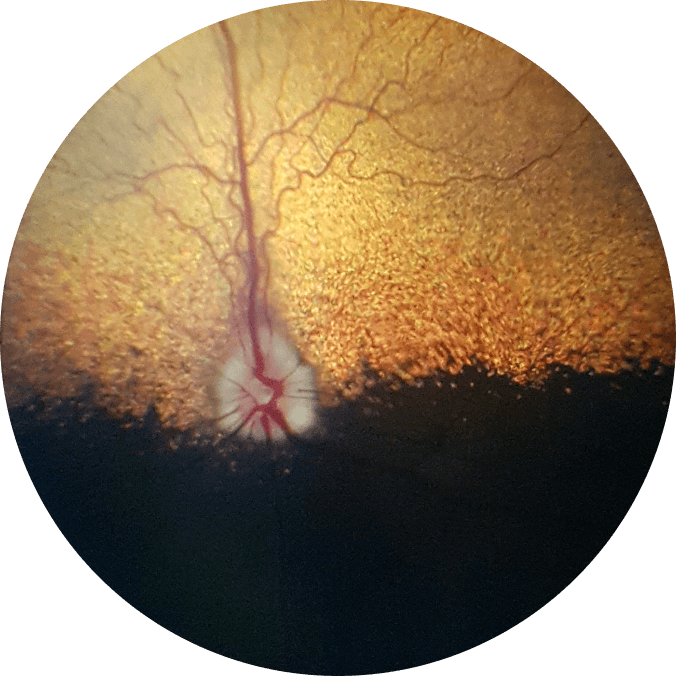

OQveT Sample Images

American Cocker Spaniel,

undilated, 2y, MC, OD